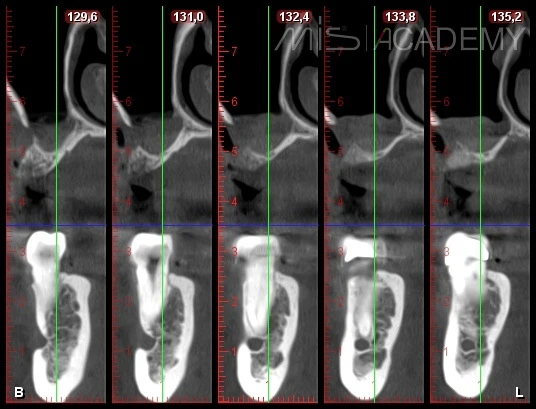

Пациентка обратилась по поводу отсутствия зуба 2.6.

Было принято решение провести ОСЛ и установку имплантата через 6 месяцев